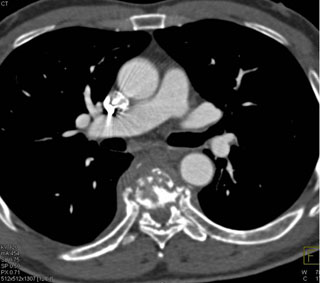

In this patient with back pain the best dx is?

lymphoma

metastatic renal cell carcinoma

osteomyelitis

prior trauma